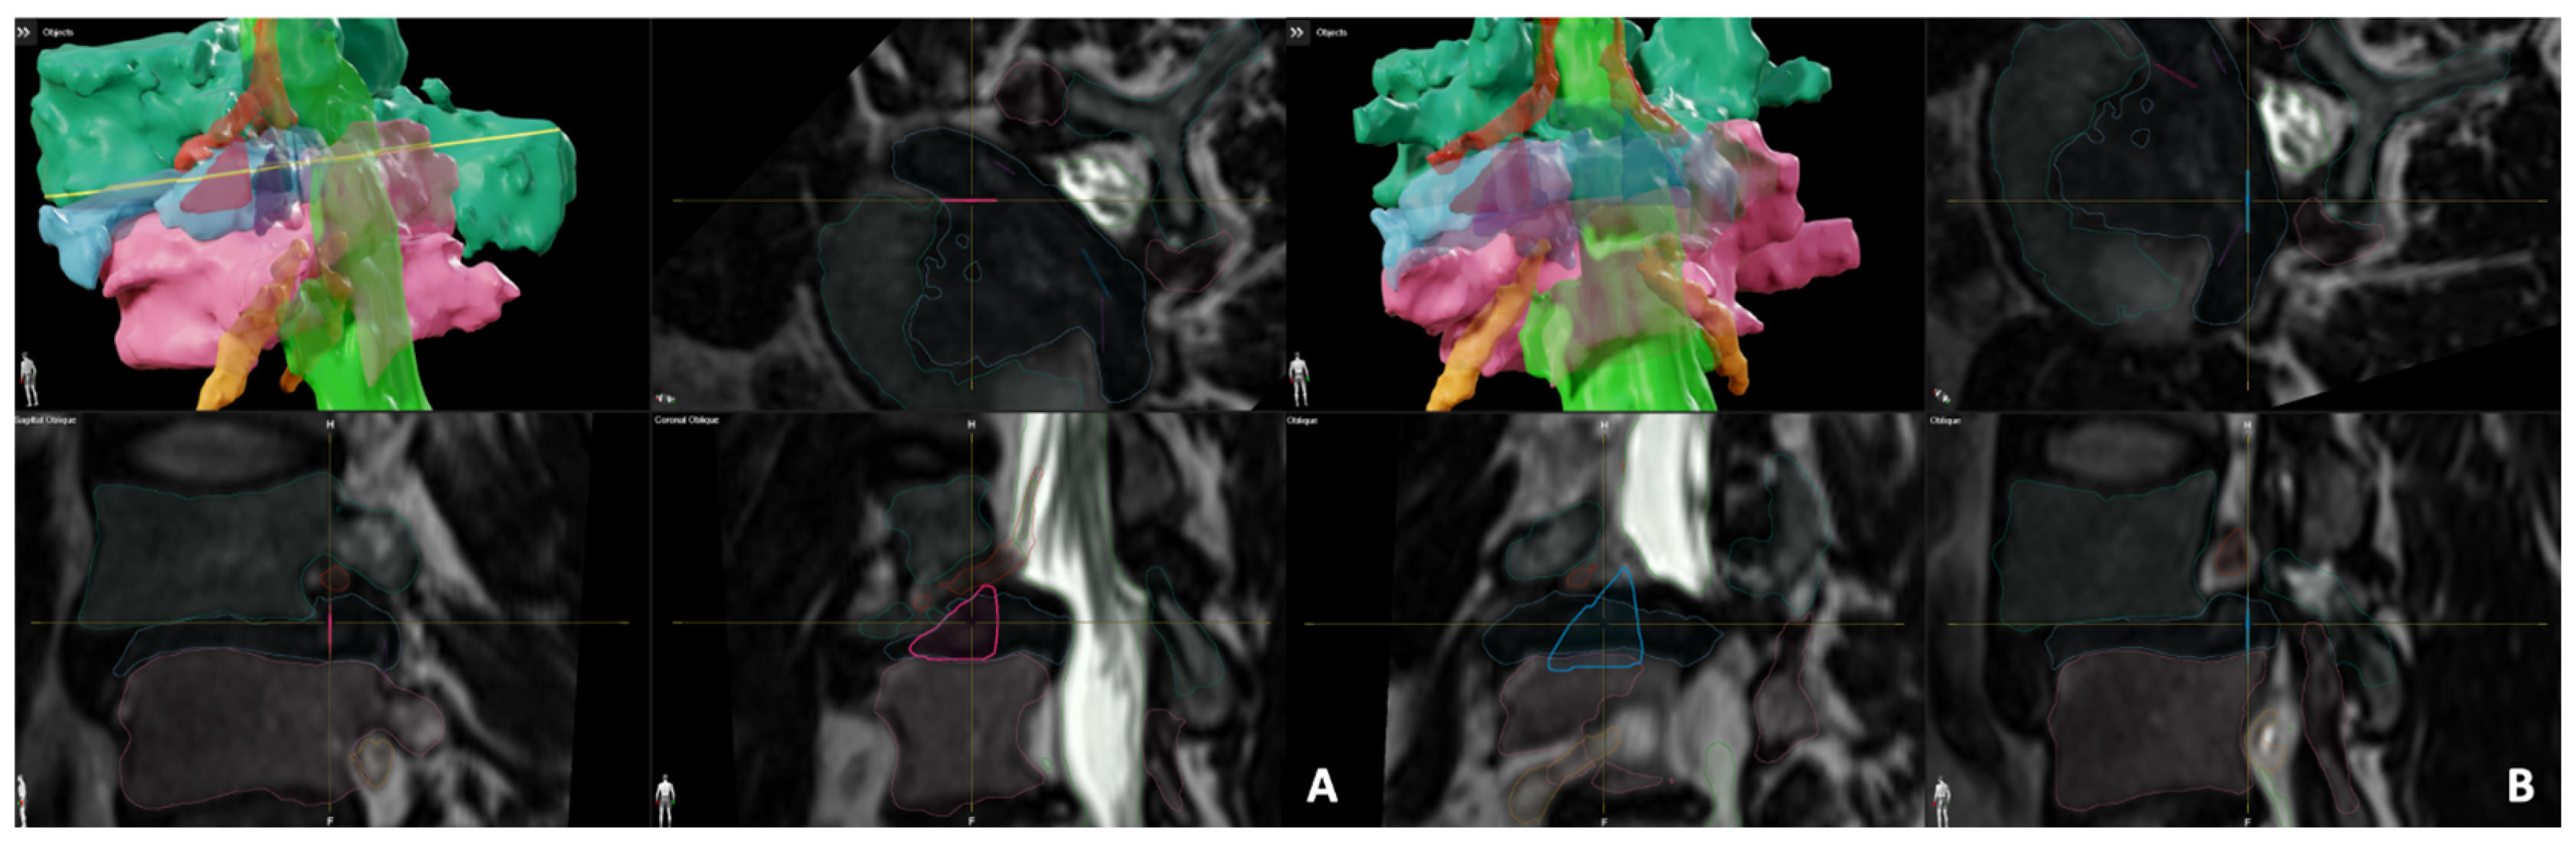

2.2. Kambin’s Triangle and TransFacet Segmentation

2.3. Pre-Operative Measurements